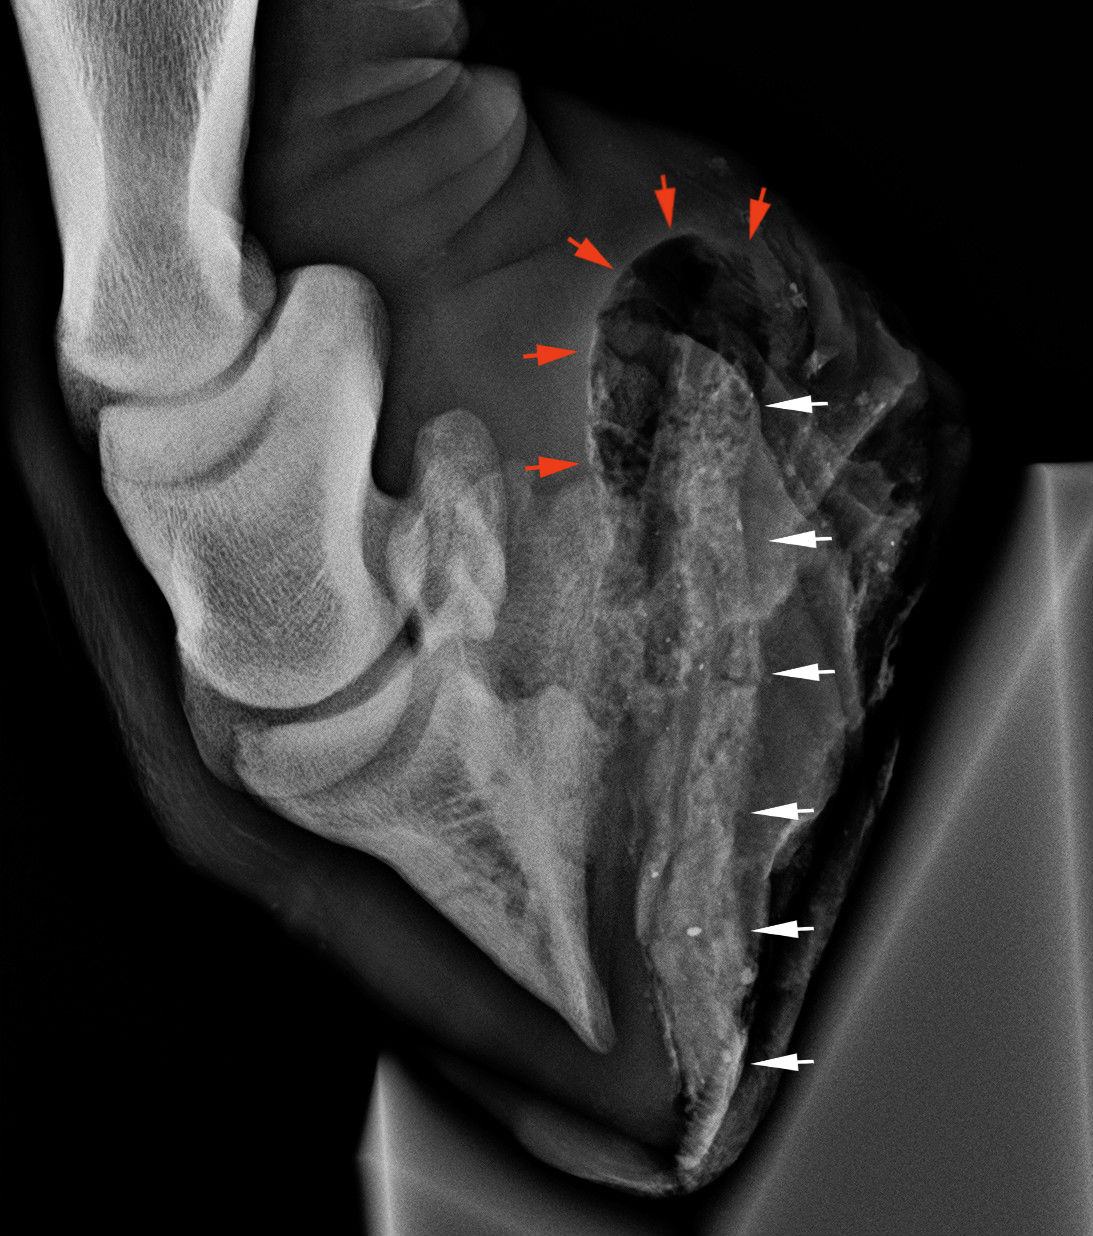

patatajyog lm

Kifejezetten nagy méretű tályog. A piros nyilak nagyméretű levegőbuborékot, a fehér nyilak a tályog üregében összenyúló földet mutatják.